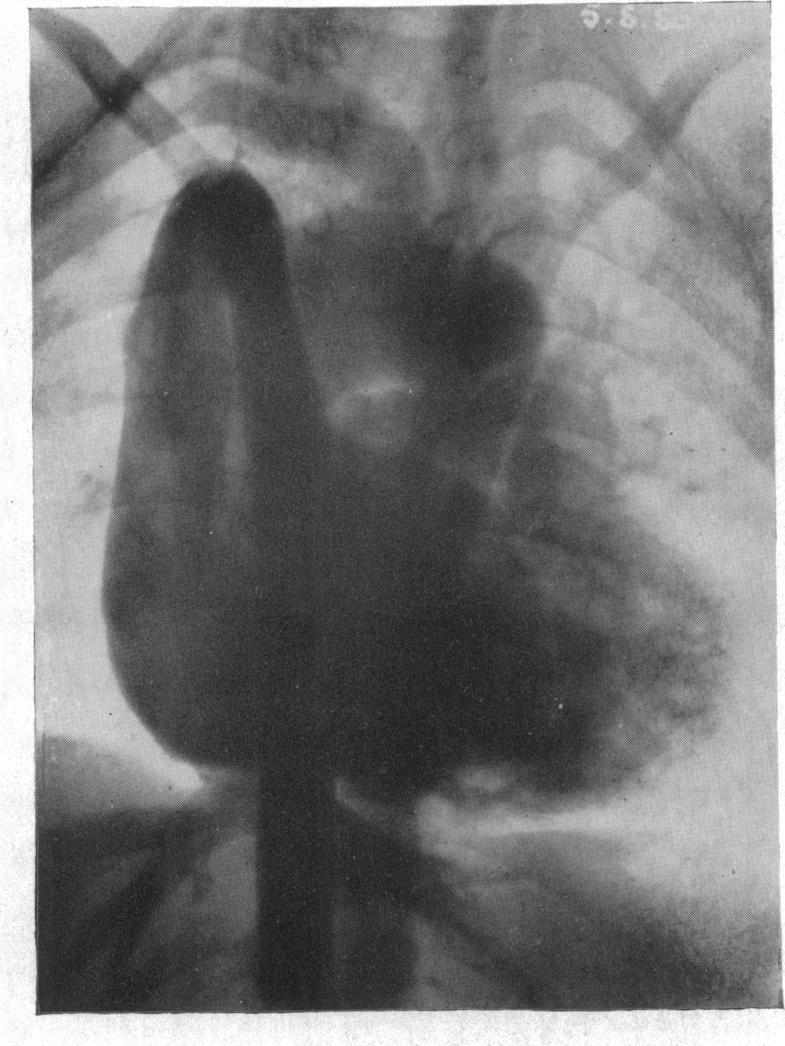

Cor biloculare.

Br Heart J. 1952 Jul;14(3):317-24. doi: 10.1136/hrt.14.3.317.